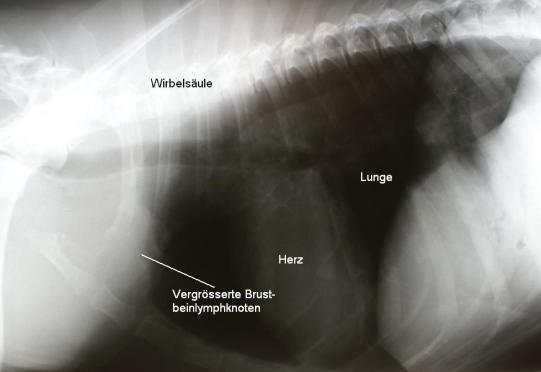

Aus drei vergrösserten Lymphknoten wird am wachen Tier mittels einer schmerzlosen Feinnadelaspiration eine Gewebeprobe entnommen. Aufgrund des starken Krebsverdachtes wird ein Bruströntgen durchgeführt, bei dem eine Vergrösserung der Brustbein-Lympknoten festgestellt wird. Ein Ultraschall der Bauchhöhle zeigt verschiedene, echoarme Knoten in der Milz; die Bauchlymphknoten erscheinen aber normal. Die Untersuchung der Gewebeproben in einem externen Labor bestätigt den Verdacht, dass „Torro“ an einem Lymphdrüsenkrebs leidet.

2 Tage nach der erstmaligen Konsultation wird die Kombinations-Chemotherapie begonnen. In einer ersten Phase (Induktionsphase) werden dem Hund drei verschiedene Medikamente verabreicht: zwei davon können von der Besitzerin in Tablettenform verabreicht werden, eines davon wird jede Woche intravenös in der Praxis appliziert. Jede Woche wird eine Blutentnahme durchgeführt, um ein zu tiefes Absinken der weissen Blutkörperchen aufgrund der Chemotherapie rechtzeitig erkennen zu können. Schon kurz nach Beginn der Chemotherapie geht es dem Hund deutlich besser und der Blutcalciumwert ist wieder im Normalbereich. Die Lymphknoten haben sich mit Ausnahme eines Brustlymphknotens auf ihre normale Grösse verkleinert; auf einem Röntgenbild ist sichtbar, dass auch die Brustbein-Lymphknoten auf ihre normale Grösse geschrumpft sind. Als Nebenwirkungen ist einzig eine vergrösserte Trinkmenge festzustellen. Da sich „Torro“ nur in einer sogenannten „Teilremission“ befindet, werden zur Chemotherapie-Intensivierung 2 weitere Medikamente eingesetzt, welche den einen vergrössert gebliebenen Lymphknoten weiter kleiner werden lassen.